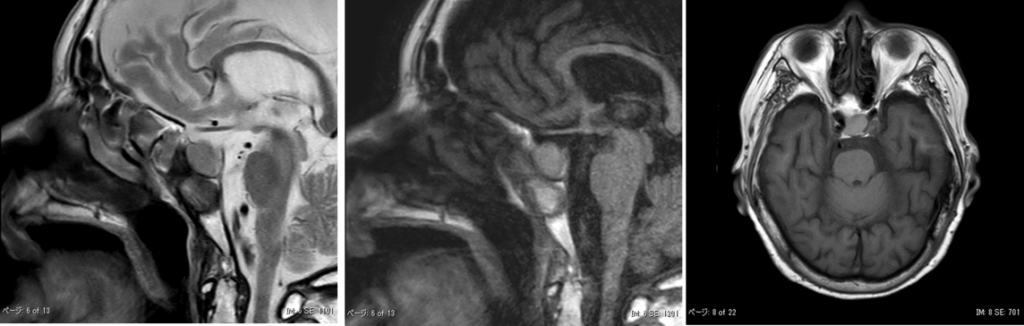

MRI画像です。

MRI上、下垂体は頭尾径14mmに腫大しています。

CT所見とあわせると血腫を見ているものと考えますが、後葉のT1WI高信号は保たれています。下垂体卒中を疑います。

腫瘍性病変混在の有無については状態が落ち着かれてから造影MRIでも評価してください。

とのことでした。

下垂体MR画像の特徴

- 信号強度の特徴(T1強調画像)

下垂体卒中のMRIにおいて最も重要な所見の一つは、T1強調画像での高信号です。

・出血の描出:

T1強調画像で高信号を示すのは、下垂体腺腫内での出血を反映しています。

・部位の特定:

通常、下垂体後葉はT1強調画像で高信号を示しますが、卒中を起こした症例では、前葉を中心に出血(高信号)が起こり、本来の後葉の高信号が後方に押しやられているような像が確認されることがあります。

- 形態的変化(サイズと圧迫)

・下垂体の増大:

出血や梗塞により下垂体が急激に増大します。今回の症例では、前後径(または頭尾径)が14mmにまで拡大していました。

・周囲組織への影響:

増大した下垂体が視神経などの周囲組織を圧迫する様子が観察されます。